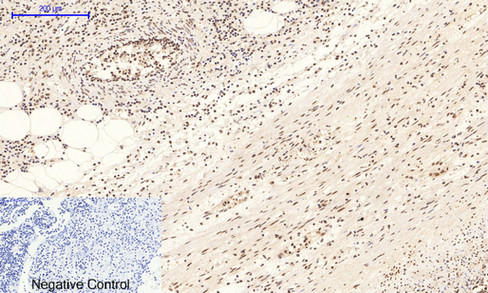

Immunohistochemical analysis of paraffin-embedded Rat-heart tissue. 1,p38 (phospho Thr180/Y182) Polyclonal Antibody was diluted at 1:200(4°C,overnight). 2, Sodium citrate pH 6.0 was used for antibody retrieval(>98°C,20min). 3,Secondary antibody was diluted at 1:200(room tempeRature, 30min). Negative control was used by secondary antibody only.